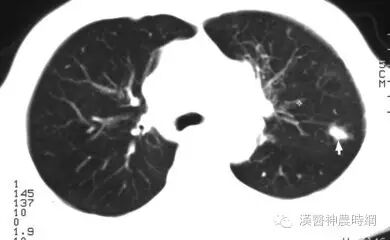

癌症的早期症状之肺癌:咳嗽是肺癌的早期症状,其特点是以阵发性刺囘激性呛咳为主,有咳不净的感觉,一般无痰或只有少量白色泡沫痰,继发感染可出现脓痰。如经抗炎治疗2周后无改善,应警惕肺癌的可能。或在原有慢性咳嗽基础上出现咳嗽性质改变,甚至伴有“气管鸣”、“气短”应予注意。肺癌的另一警号是间断性反复少量血痰,或痰中带血丝。此外,还出现胸背痛、胸闷、发热等症状。